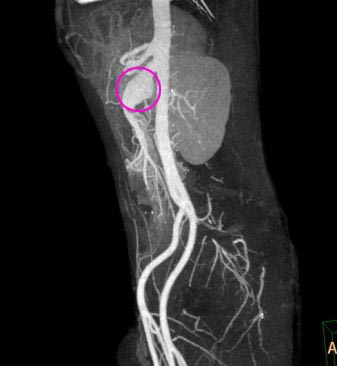

术前(红圈处为“动脉瘤”)

术后(红圈处为“封堵器”,蓝圈处为“人工血管桥”)